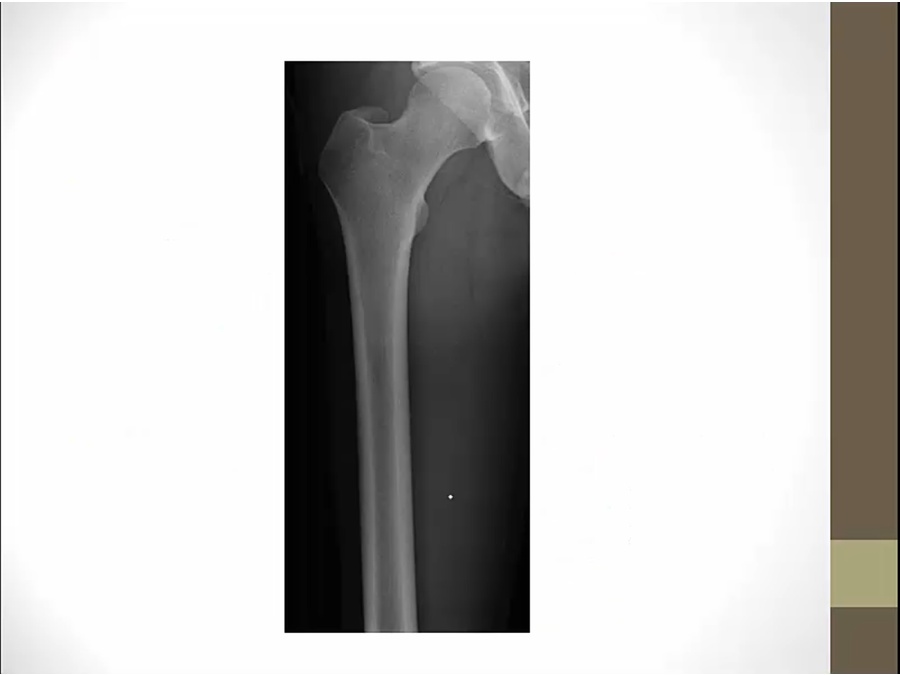

center: medullary cavity

top: porous, trabeculated, end of long bone

2 ossifications grow towards each other and trap epiphyseal plate

layer of cartilage trapped = growth plate